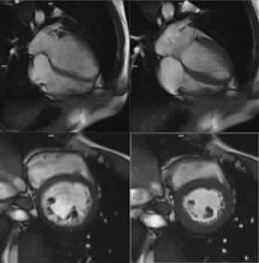

L'IRM cardiaque:

L'IRM (Imagerie par Résonance Magnétique) est un examen non irradiant (sans rayon X), qui permet d'analyser la structuer du cœur (myocarde, péricarde, ...) et le comportement du muscle cardiaque en reproduisant des effets semblables à ceux d'un effort (Dobutamine) et d'une dilatation des artères (Adénosine). L'appareil est constitué d'un lit d'examen et d'un gros anneau. Dans la plupart des cas, un produit de contraste (à base de Gadolinium) est injecté par voie intraveineuse pour améliorer la qualité des images obtenues. Cet examen présente l'avantage de donner des informations très précises.

Cet examen peut être employé notamment pour :

- Diagnostiquer une anomalie de la fonction du muscle cardiaque ou un déficit de la vascularisation comme par exemple, un rétrécissement des artères coronaires.

- Rechercher une éventuelle cicatrice du muscle cardiaque, un signe d'infarctus.

- Rechercher une tumeur au niveau du muscle ou des cavités cardiaques.